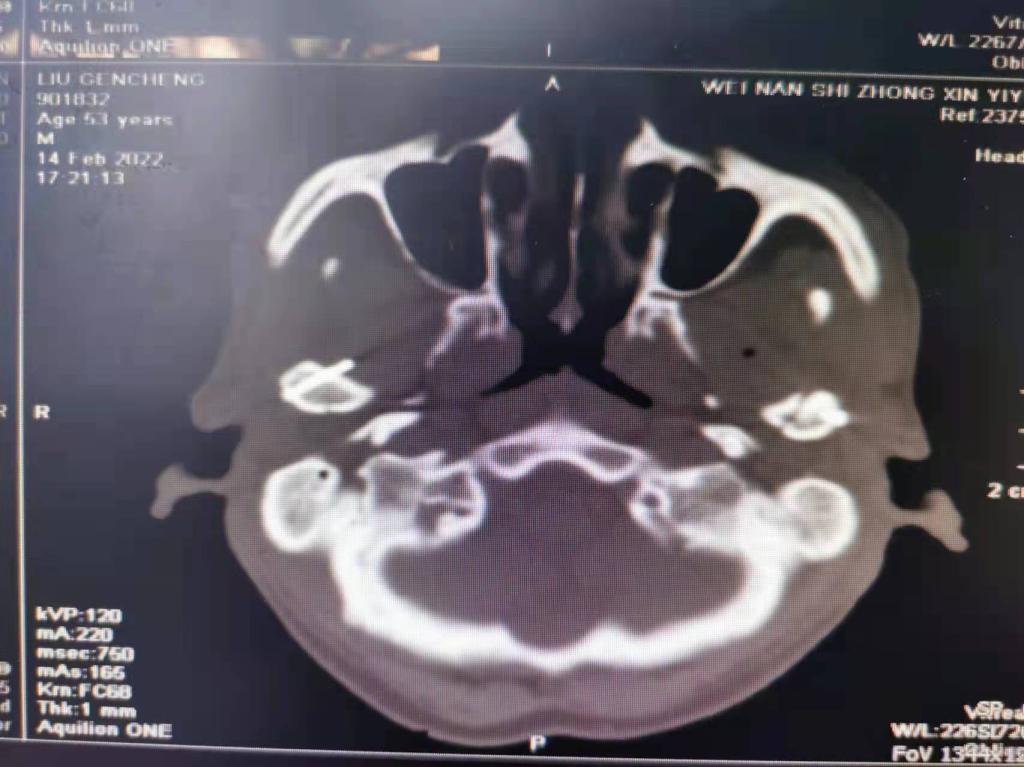

据了解,53岁的患者刘先生在1月25日当天走路不慎摔倒致下颌损伤,造成颏部软组织裂伤和张口困难,前往当地卫生院进行颏部裂伤清创缝合术。术后辗转到乐鱼在线登录入口口腔科门诊就诊,并进行颌面部CT检查提示为下颌颏部正中和双侧髁状突骨折,双侧下颌升支高度不一致,右侧较左侧变短1cm,张口重度困难,咬合关系错乱。刘先生因考虑在春节过后再入院治疗,于2月8日再次前来口腔科以“下颌骨骨折”收治人院。

口腔科主治医师蔺非非为患者入院后进行完善术前常规检查和颌间牵引恢复咬合关系。科主任李瑞春结合患者实际病情和检查结果认为,患者的髁突骨折在下颌骨骨折中所占比例较高,约为17.0%-36.3%。髁突骨折时,耳前区有明显的疼痛,局部肿胀、压痛。通过手指深入外耳道或在髁突部触诊,如张口时髁突运动消失,可能有骨折段移位。双侧低位骨折时,2个髁突均被翼外肌拉向前内方,双侧下颌支被拉向上方,可出现后牙早接触,前牙开秴。髁状突骨折易引起下颌后缩,张口困难,咬合关系错乱,关节强直等并发症。考虑患者系陈旧性骨折应尽早实施手术,避免骨折导致的张口困难、关节强直等并发症。因患者已经错过最佳治疗时期,决定尽快为患者进行手术治疗。

科主任李瑞春和主治医师蔺非非经过缜密的术前讨论和充分评估,手术在全身麻醉下进行,术中克服术野狭小操作不便困难,将下颌骨骨折完好对位,顺利地完成了"双侧髁状突和下颌颏部正中骨折切开复位内固定术"。术后检查患者面部对称,双侧下颌升支高度一致,咬合关系已恢复。